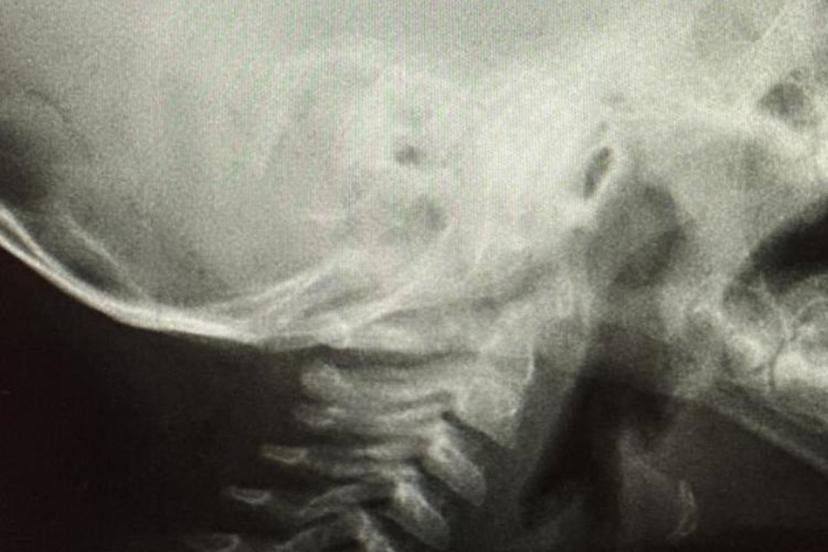

Solunum yollarına yabancı cisim kaçmasının da önemli bir risk olduğuna dikkat çeken Özkaya "Solunum yollarına yabancı cisim kaçması da günlük hayatta sık karşılaşılan ve hayati tehlike oluşturabilen durumlardan biridir. Özellikle üç yaşına kadar olan çocuklara çerez, fındık, fıstık, çekirdek gibi sert gıdaların verilmemesi gerekmektedir. Bu gıdalar solunum yollarına kaçarak ciddi nefes darlığına neden olabilmektedir. Böyle bir durumla karşılaşıldığında, mümkünse Heimlich manevrası uygulanmalı ve 112 Acil Servis eşliğinde en yakın sağlık kuruluşuna başvurulmalıdır. Bu tür vakaların operasyon gerektirebileceğine dikkat çekilerek, özellikle yemek borusunda kalan disk pillerin son derece tehlikeli olduğu vurgulanmaktadır. Disk piller, çocukta belirgin bir şikâyet olmasa bile kısa sürede yemek borusunda yanıklara ve delinmelere yol açabilmekte, hayati risk oluşturabilmektedir. Bu nedenle acil olarak ameliyathane ortamında çıkarılmaları gerekmektedir." şeklinde konuştu.